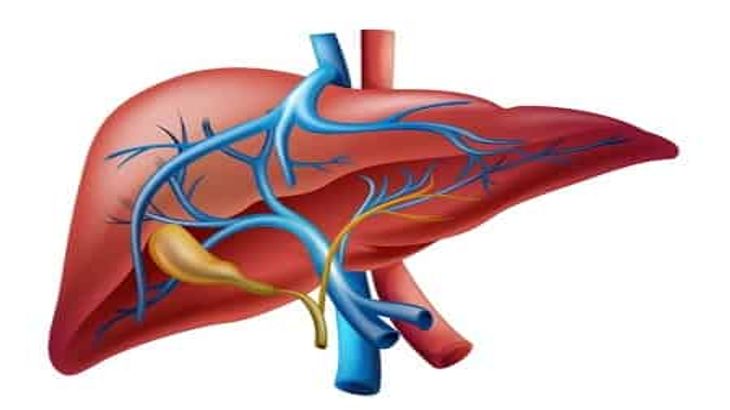

A liver transplant replaces a diseased or failing liver with a healthy donor liver. In liver transplant Singapore, the procedure is carefully evaluated and performed by specialists such as hepatologists, transplant surgeons, and multidisciplinary care teams who ensure each step is precise and patient-centred.

During liver transplant Singapore, surgeons remove the diseased liver and replace it with a healthy donor liver. The procedure may take 6–12 hours, depending on complexity.